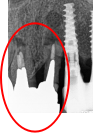

左下、ブリッジの支台になっていた奥のほうを抜歯したままになっている。ここのところを何とかしたい。

治療内容

ブリッジの奥に伸びていた部分を削り取り、インプラントを2本入れました。

所感

左下ブリッジのところを切り離し、奥を抜歯したままになっていました。このままでは、ブリッジの前方の支台になっていた歯に負担がかかり、将来抜歯になる可能性があることをお話ししました。歯がないところを補う方法には、部分入れ歯かインプラントがあることを説明すると、自分の歯と同じ感覚で食事ができるインプラントを選択されました。X-Guideを使用し埋入しました。口を大きく開けることができない方でしたので、X-Guideの長所のうちの一つを活かすことができました。

インプラント2本:¥363,000×2本=¥726,000(税込)

Before

青丸の部分を削り取りました

After